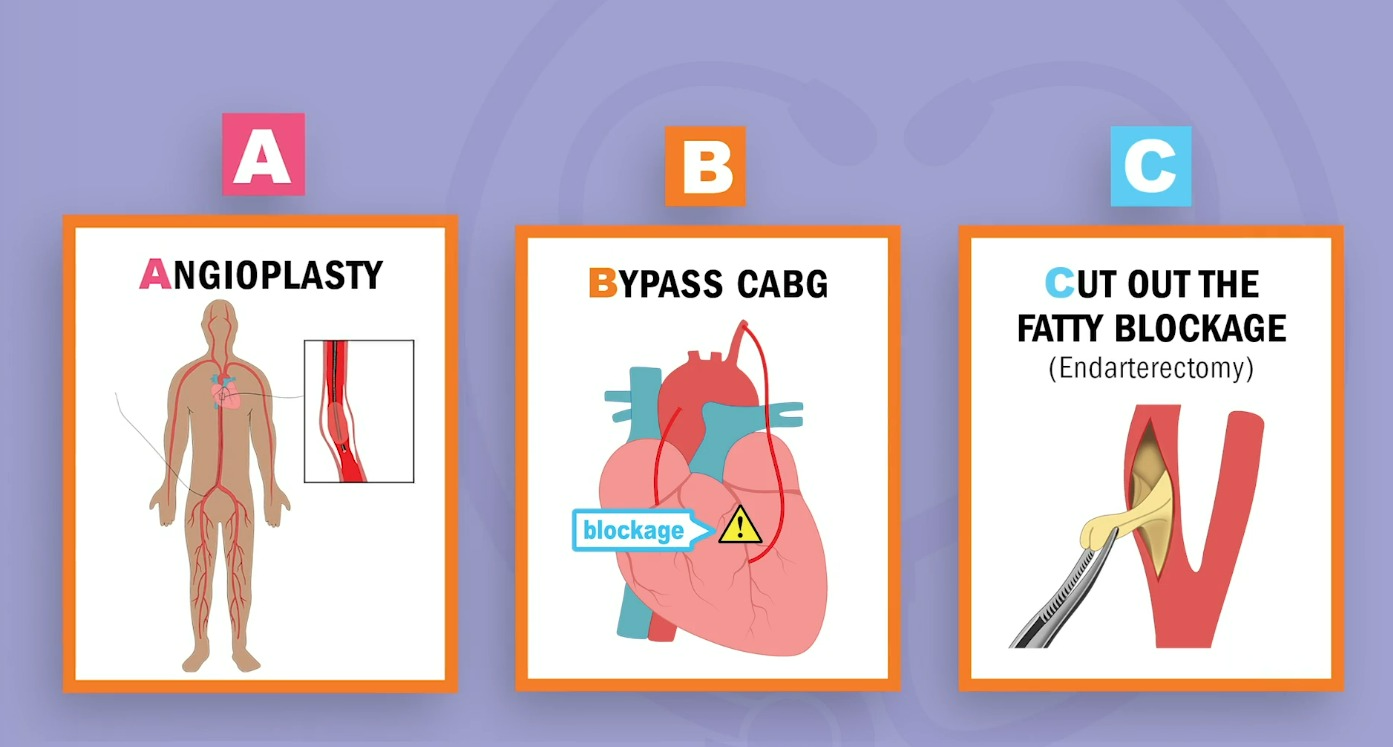

✔️Cath Lab 시술

PCI : percutaneous Coronary Intervention

1. Aterio, Angio "-plasty" "-gram"

2.Bypass